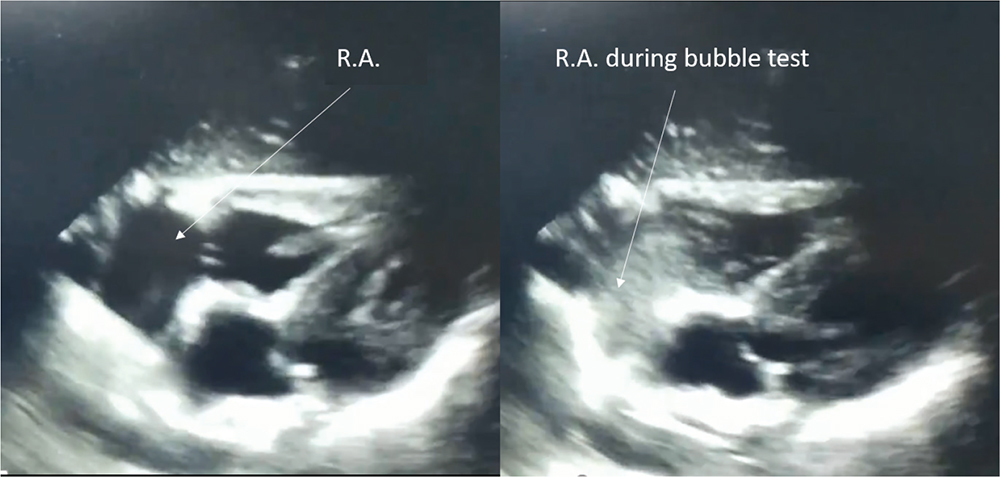

The technique still considered the most reliable and cost-effective for verifying the position of the PICC tip (tip location) at the cavoatrial junction is the intracavitary electrocardiogram (1,7,8,12). For the critical care physician, generally well skilled in ultrasound diagnostics, the use of transthoracic echocardioscopy for the PICC tip location may be faster and easier (1,8). A four-chamber cardiac scan allows to visualize the right atrium, the infusion via PICC of a few milliliters of normal saline mixed with a small amount of air allows to measure the delay between injection and visualization of the fluid in the right atrium (bubble test). Although in the literature a maximum time of up to 2 seconds is reported, a delay of 1 second or less is considered a reliable indicator of the correct positioning of the tip (8,13) (Fig. 2).